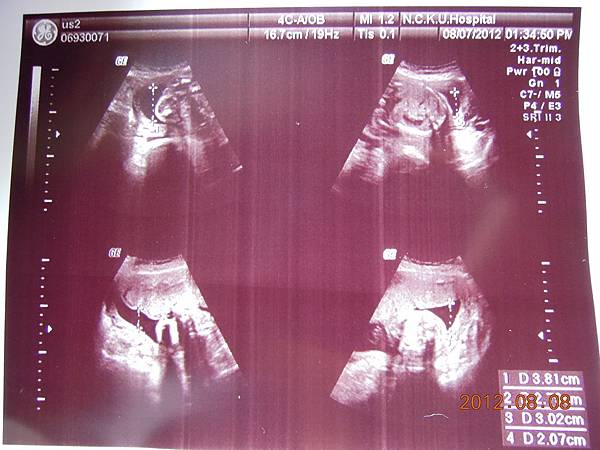

除了比較明顯的骨頭可以看的出來,其實我們看不太懂,但是他精熟的技術很快把每個部位的大小都量測出來,我躺在床上看著上頭的螢幕,慢慢欣賞他的每張超音波照片~~

可以看到的是在逼逼的上方剛好被胎盤擋著,比較看不到他的正面,除了肛門無法看到(怕沒有肛門),醫師說現在看不到,小雞雞也沒照他的大小(我怕他發育不良),其他身體器官包括腦部剖有量測他的大小及羊水多寡(我怕像上次一樣羊水太少),今天量出來是12,喔彌陀佛~~

大約檢查了有四五十分鐘,也數了他的手指腳趾,看起來是沒異狀,就叫我等下把報告拿過去門診給游醫師看,還給我ㄧ堆照片,就是下面那些~~

這是他給我的報告,都是一些代號,游醫師說明很快,不過我聽他說沒問題,就比較放心,裡面有把每個器官大約生長到幾週做個說明,大致都在22~24周,逼逼體重約697g~

高層次超音波報告~~

接下來就是他的一堆檢查照片啦~~